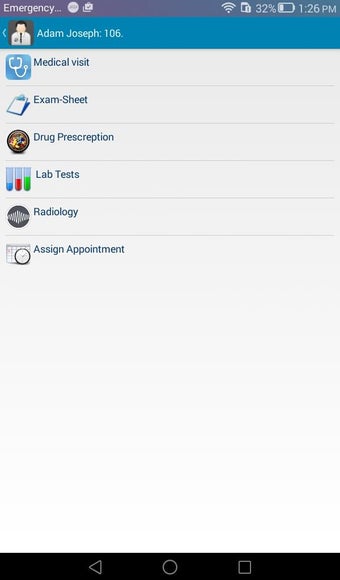

The Android Medical Records App by MedClin is a free medical records tracker app that allows users to store anamnesis, patient records, patient history, and health information. It is easy to use and provides numerous features such as username and password authentication, exporting medical data to Excel Sheet, and the ability to attach medical documents of any type. The app also has a smart search feature that allows users to search for patient information by name or ID, and even capture a photo for their profile.

In addition, the app has a blood pressure module that measures systolic, diastolic, and pulse, and allows users to export blood pressure reports to either PDF or graphs. The app also has a blood glucose (sugar) module that records blood sugar values and allows users to export blood glucose reports to either PDF or graphs. Users can also send blood pressure and blood sugar reports to their doctor. The app is compatible with multiple screens, including phones and tablets, and works on Chromebook systems. Overall, the Android Medical Records App is a great tool for patients and physicians alike for managing patient information and medical records.